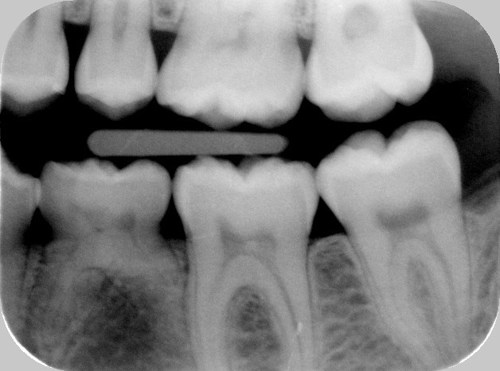

Normalt ligger de nye tænder lige nedenunder mælketænderne, som ses på første billede. På andet billede mangler anlæg til den blivende tand.